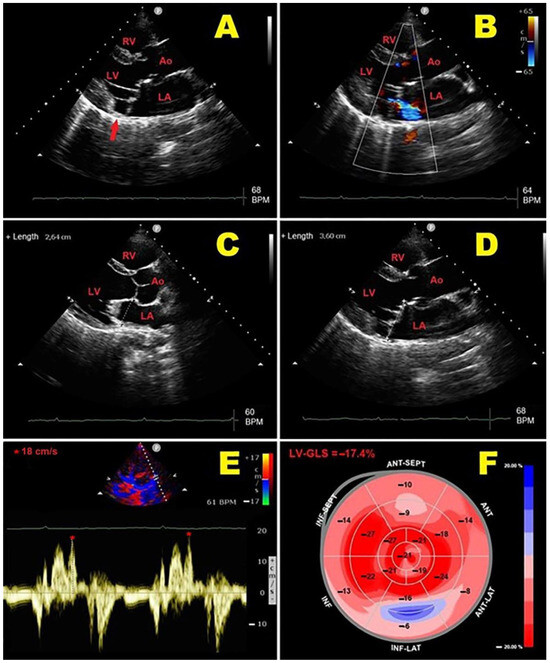

- Sonaglioni, A.; Nicolosi, G.L.; Rigamonti, E.; Lombardo, M. The influence of chest wall conformation on myocardial strain parameters in a cohort of mitral valve prolapse patients with and without mitral annular disjunction. Int. J. Cardiovasc. Imaging 2023, 39, 61–76. [Google Scholar] [CrossRef] [PubMed]

| Sonaglioni, A. et al. (2023) [31], Italy | 93 | 54.2 | 50.5 | TTE, STE | Prospective | 34.4 | ↓ A-P thoracic diameter; ↑ myxomatous MVP ↓ cardiac chambers cavity sizes ↔ LVEF; ↓ LV-GLS and LV-GCS |